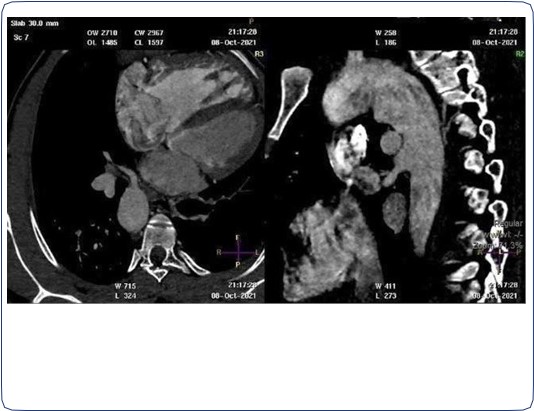

Two arterial supplies to the right lung arising from the descending aorta. A dominant one arising from the medial side that supplies the right upper lobe (Figure 3). Another smaller branch supplies the right middle and lower lobes (Figure 4).

Small blind-ended artery arising from the aortic arch at the take-off point of the left brachiocephalic artery (Figure 5) with non-visualization of left main pulmonary artery (Figure 3A). Multiple small arterial collaterals at the left hilum supplying the relatively hypo-plastic left lung (Figure 3A).

Right ventricular dilatation with myocardial hypertrophy (Figure 4).

Figure 3: Contrast-enhanced CT chest axial (A), sagittal and coronal (B) views, showing an arterial supply to the right upper lobe arising from the descending aorta. Also there is an absent left pulmonary artery with multiple small collaterals at the left hilar region. Relative hypo-plastic left lung.

Figure 4: Contrast-enhanced CT chest axial and sagittal views, showing another small arterial supply to the right lung arising from the descending aorta. Dilated right ventricle with right ventricular wall hypertrophy.